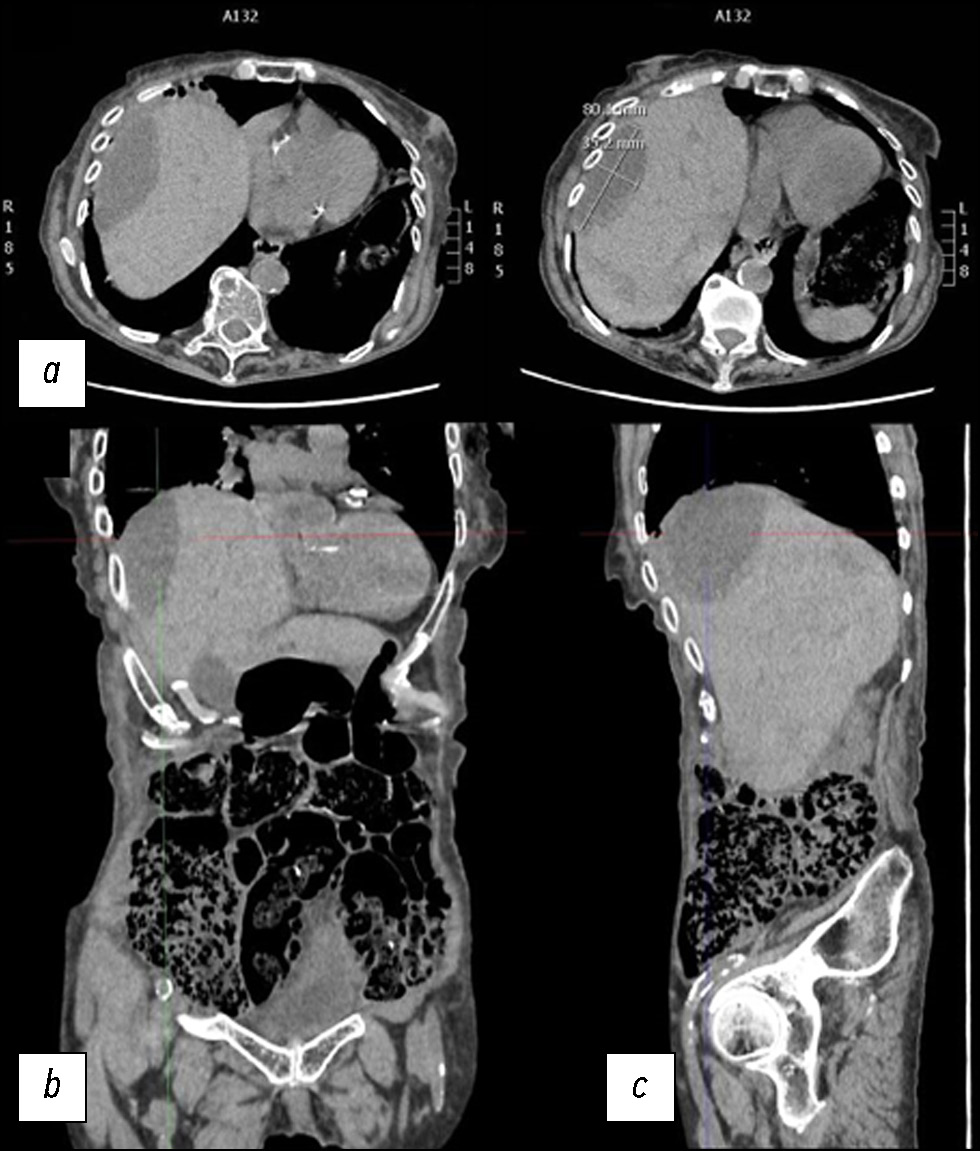

A case of spontaneous liver rupture and the role of imaging: from computed tomography to interventional treatment

Hepatic parenchymal rupture is a rare but potentially fatal condition that can be caused by trauma, iatrogenic factors, spontaneous causes, etc. This case report describes the diagnostic and therapeutic steps employed in a patient with spontaneous hepatic parenchymal rupture. An older woman came to the emergency department with diffuse stomach pain. After clinical evaluation, she underwent computed tomography. The first computed tomography did not reveal a full-blown parenchymal rupture. Owing to data ambiguity, indicating that the abdominal discomfort could be caused by renal or biliary colic, obtaining an early diagnosis was very difficult. In truth, only few hypodense oval shapes with characteristic suprafluid densitometry were found in the liver parenchyma. However, after a few days, the discomfort persisted, and as the condition worsened, the patient underwent additional radiological examinations, which revealed the rupture of the liver parenchyma that required arteriography, and a long hospital stay until clinical resolution.